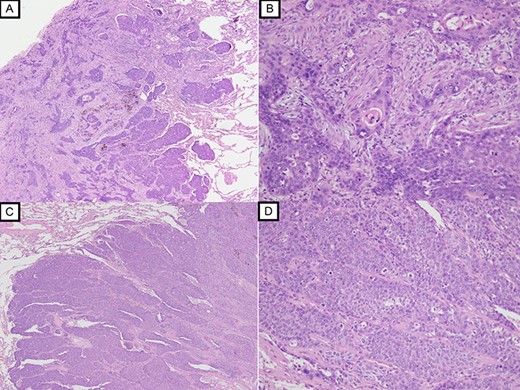

Since no other findings suggestive of distant metastasis were found, partial left lung resection was performed for the two nodules. Both were diagnosed as squamous cell carcinomas (Fig. 4). Furthermore, 5 months after left lung resection, a metastatic liver tumor was found, which was also surgically resected. Finally, 10 years and 4 months after esophagectomy, 3 years after the first lung resection and 1 year after hepatectomy, the patient died due to peritoneal dissemination.

Histopathological examination with HE staining revealing squamous cell carcinoma in S1 + 2 nodule (original magnification ×20 (A), ×100 (B)); histopathological examination with HE staining revealing poorly differentiated squamous cell carcinoma in S9 nodule (original magnification ×20 (C), ×100 (D)).